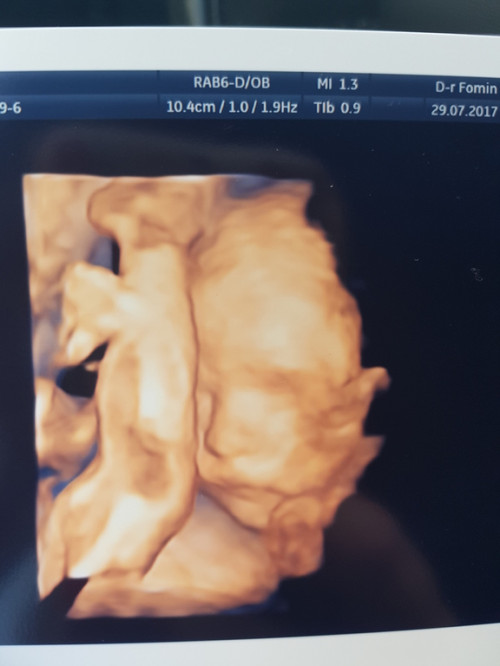

А вот и наши малыши!

8).

6 фото просто красота😍😍😍 отдала за него голос. Малыш прелесть! И эта ладошка...😍